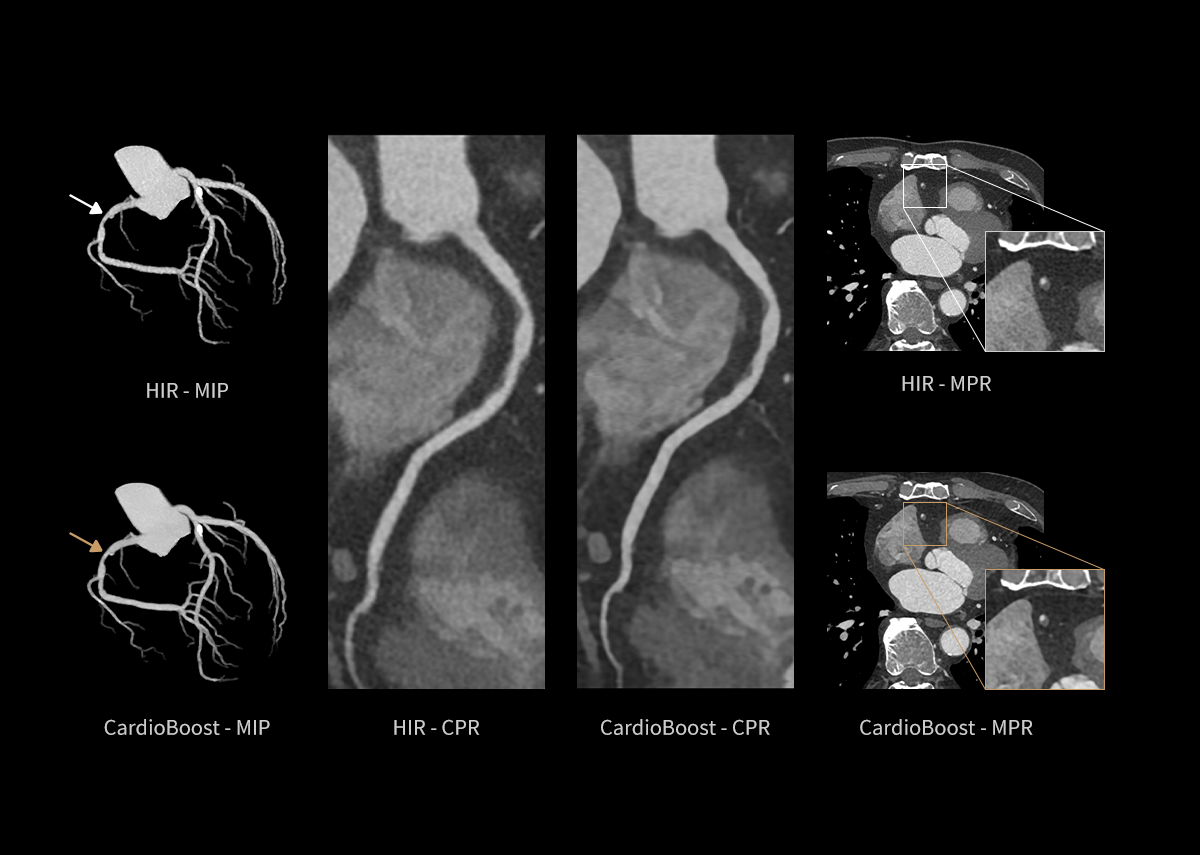

AIIR* – AI Iterative Reconstruction

Throughout the iterative loop of forward and backward projection between the raw data domain and the image domain, AIIR consistently takes into account the accurate modeling of optics, noise, anatomy, and physics statistics. Additionally, AIIR integrates deep learning-based de-noising technology, supplanting the conventional regularization role of MBIR in the optimization reconstruction process.

In brief, AIIR utilizes deep learning-based AI technology to attain robust noise reduction and natural image texture, while incorporating MBIR technology to achieve precise anatomical structure representation and artifact suppression. This technique surpasses the limitations of using either MBIR or deep learning reconstruction (DLR) independently.